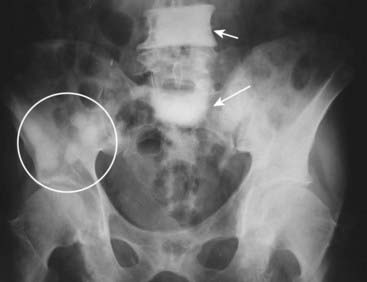

image

Figure 21-3 Diffuse metastatic disease from carcinoma of the prostate.

The bones are diffusely sclerotic. You can no longer see the normal trabeculae or the junction between the medullary cavity and the cortex as the medullary cavities have been filled in with osteoblastic metastatic disease that obscures these normal boundaries and increases the overall bone density. Contrast this picture with that of Paget disease of the pelvis (see Fig. 21-12).

Figure 21-6 Focal sclerotic metastases from carcinoma of the prostate.

There are sclerotic lesions seen in the L4 and S1 vertebral bodies (solid white arrows). It is no longer possible to distinguish the junction between the cortex and the medullary cavity in either of those vertebral bodies. Also present are multiple sclerotic lesions in the right ilium (white circle) and scattered throughout the pelvis. Sclerotic lesions in bone are a common finding in carcinoma of the prostate.